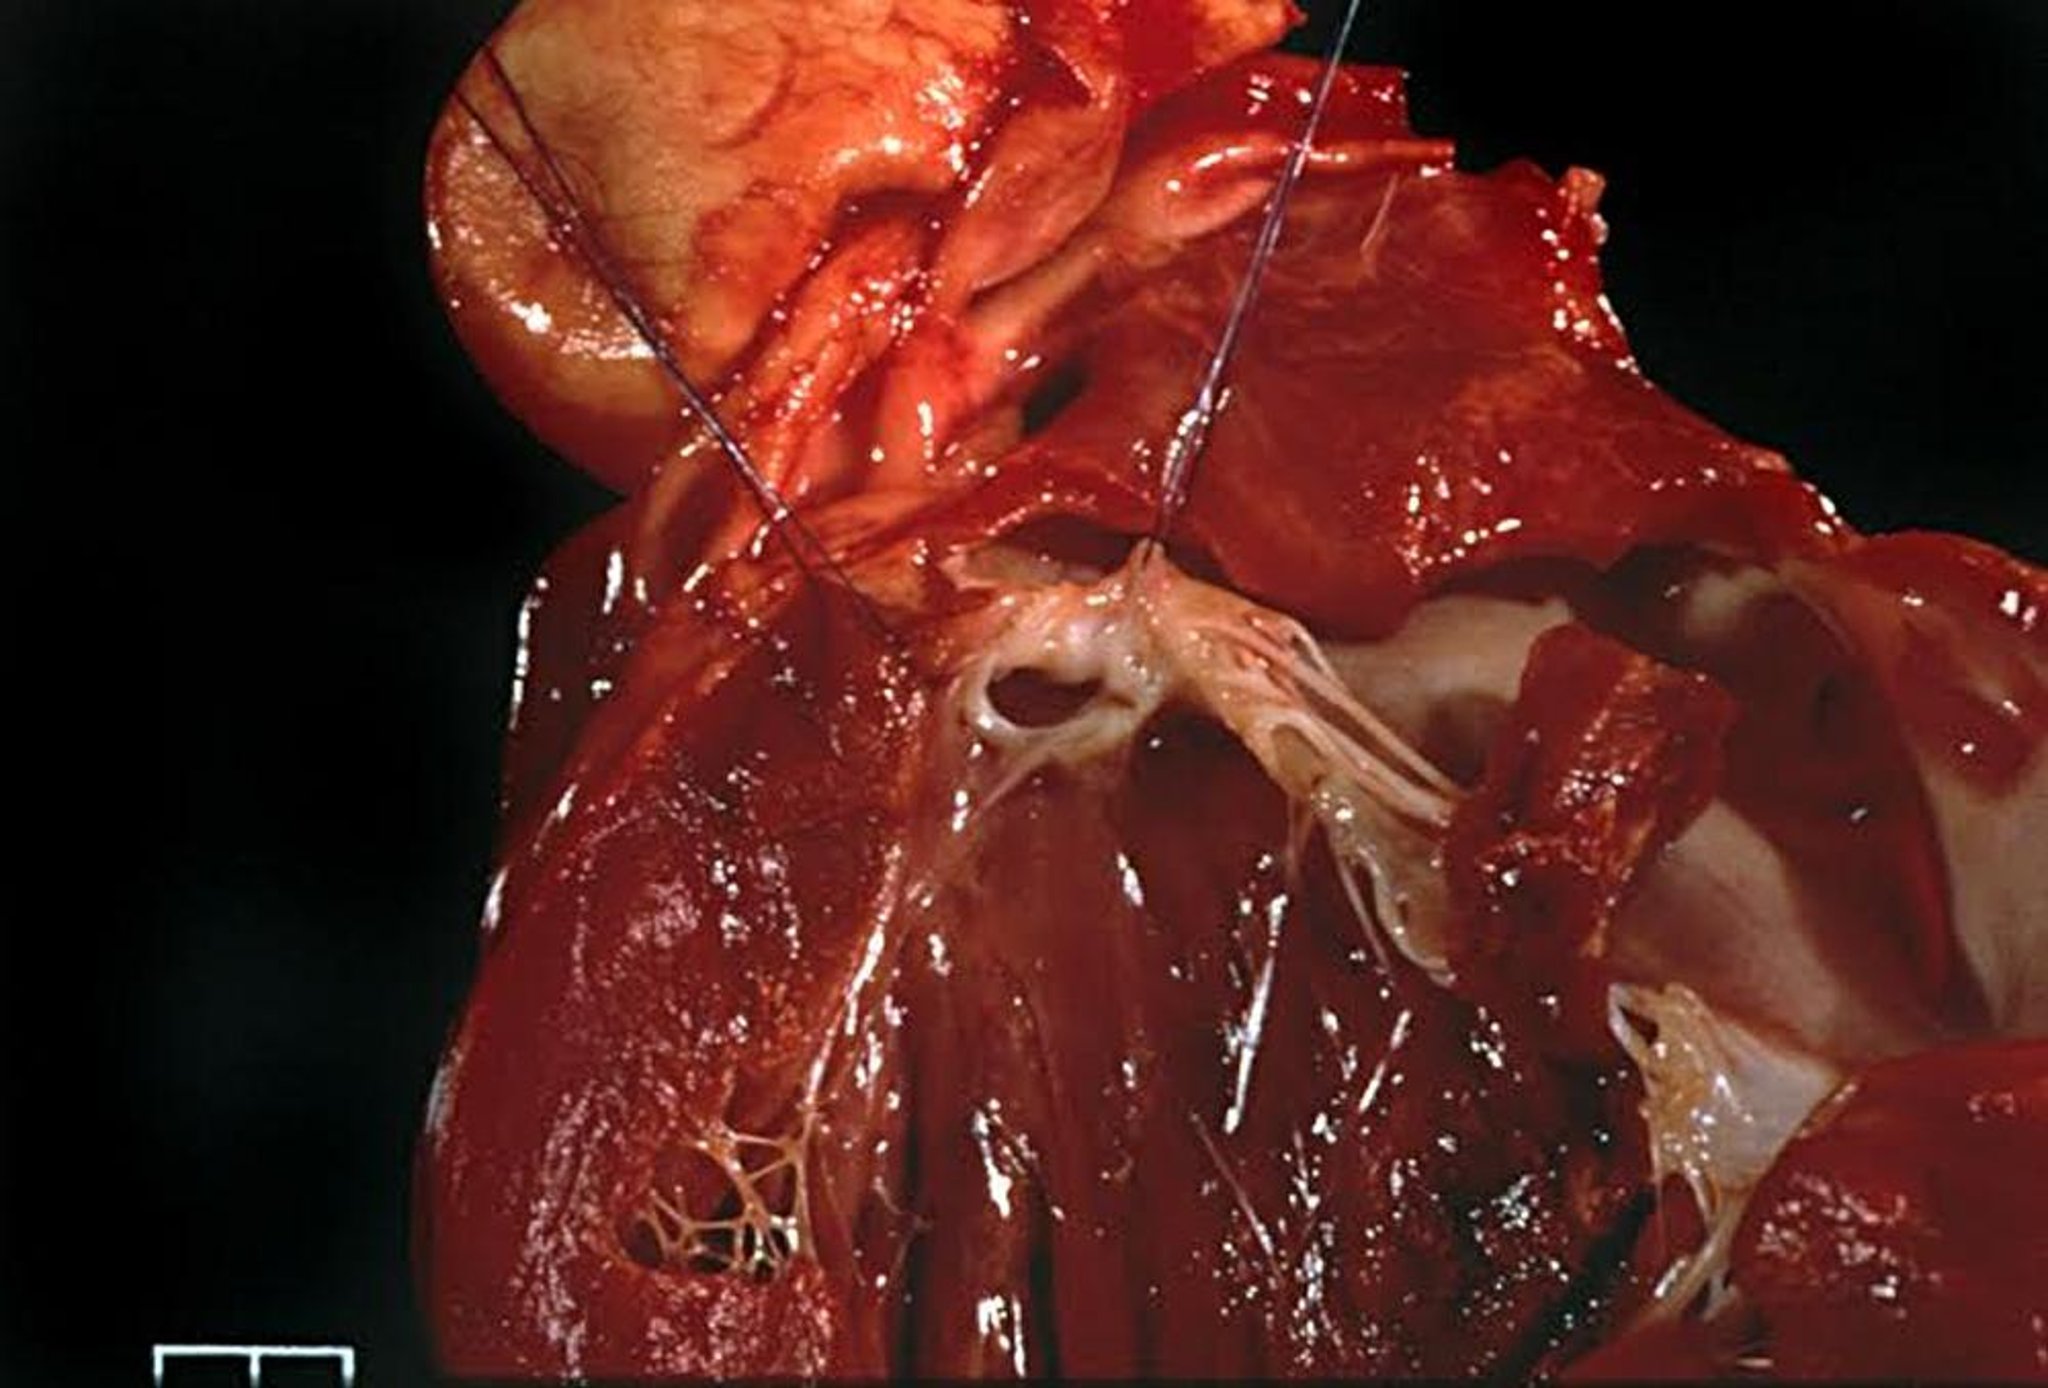

Estenosis subaórtica, perro

Tracto de salida del ventrículo izquierdo de un perro con estenosis subaórtica grave que muestra un anillo subaórtico fibroso e hipertrofia concéntrica del ventrículo izquierdo.

Cortesía del Dr. Bruce Keene.